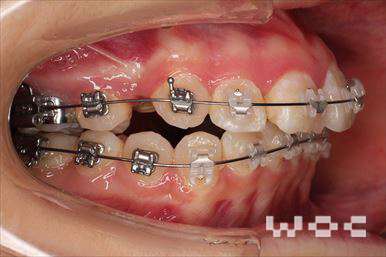

出っ歯エッジワイズ装置

特に装置の希望はなかったので、エッジワイズ装置を選択。

歯の移動量が大きいので歯根吸収の可能性がありましたが、目立った吸収は見られませんでした。-

治療中1

- 年齢:17歳女性

- 主訴:出っ歯、前歯のガタガタが気になる

- 基本矯正料金:78万円

- 治療期間:1年2ヶ月

- 抜歯部位:上顎両側第一小臼歯